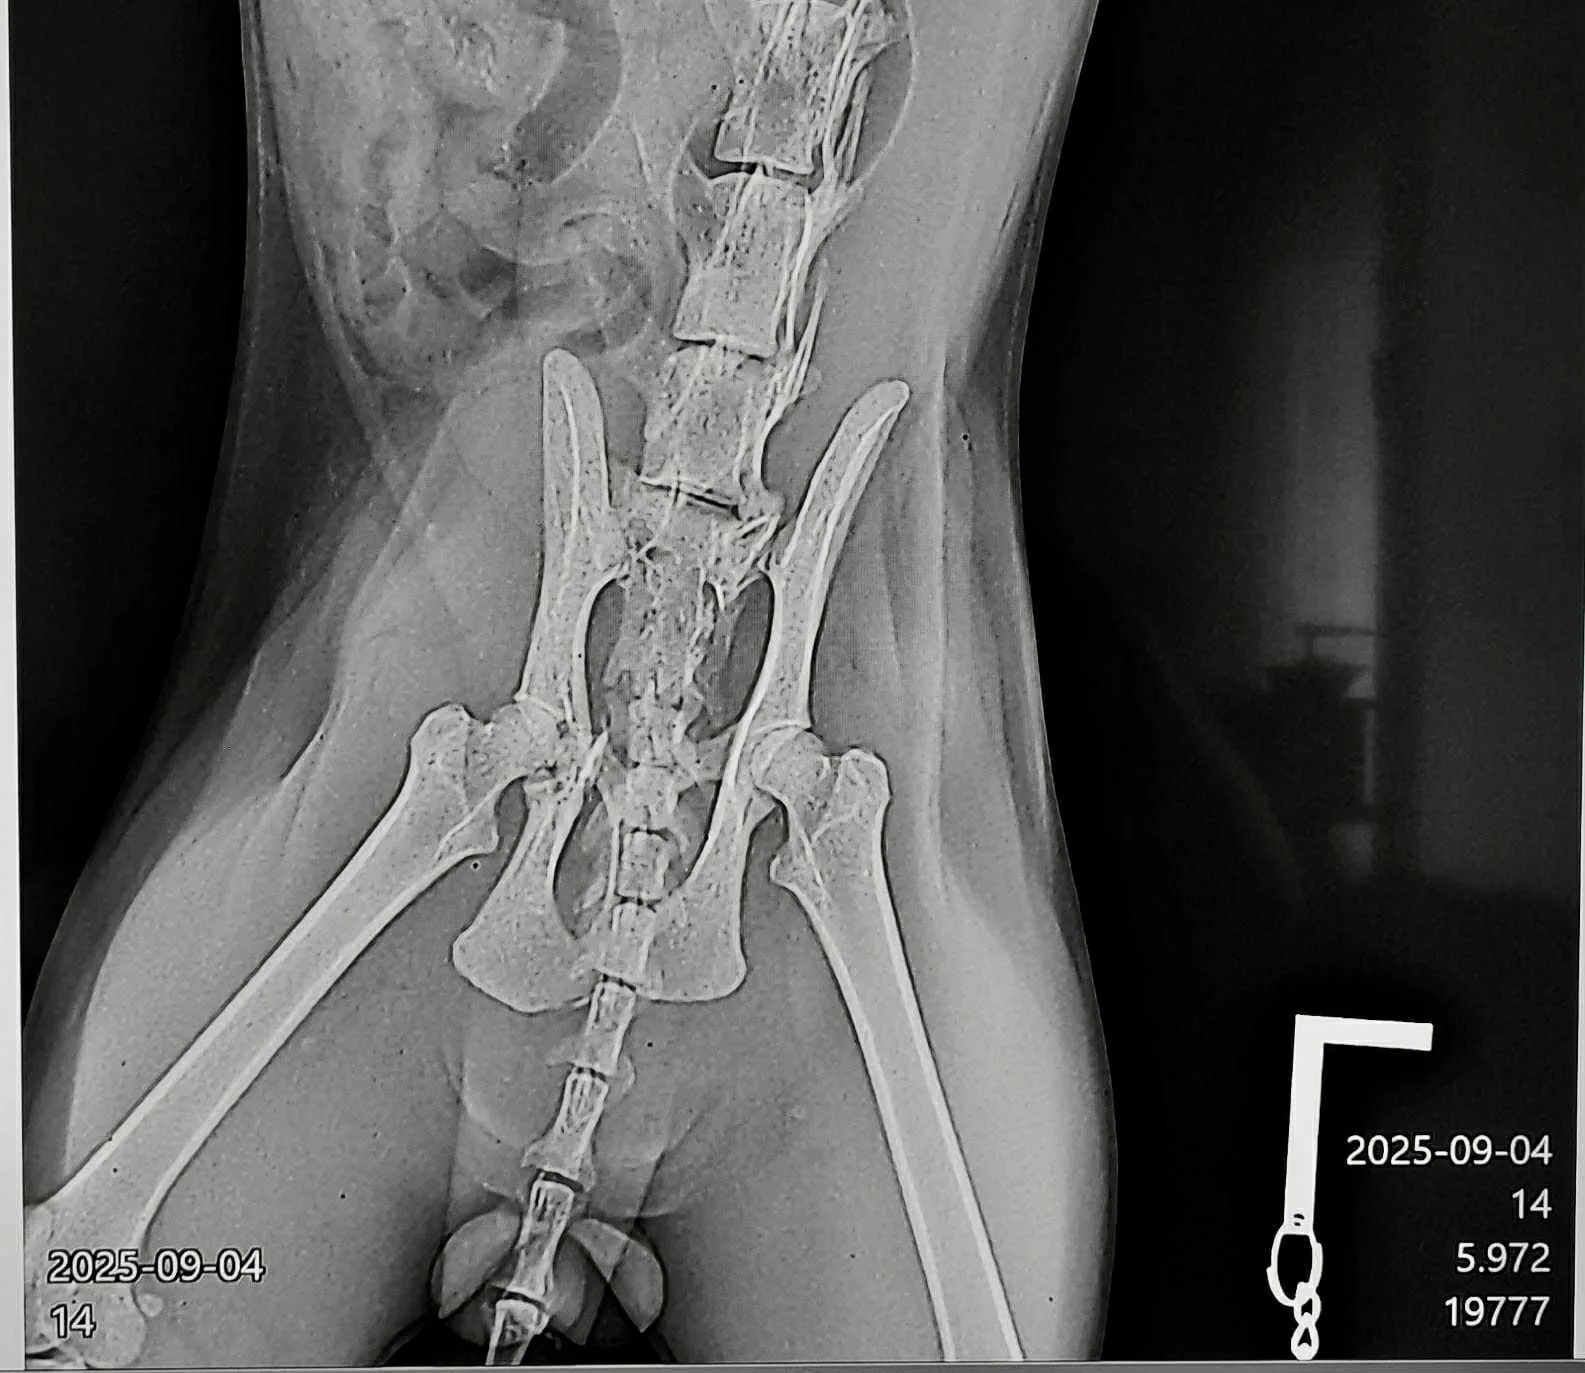

Котаракът е със съществени контузии и сега е приет в болница и на обезболяващи. Необходима е незабавна интервенция на стойност към 1000 лв., както и човек, който да се грижи за него в домашни условия за интервал от към два месеца, до момента в който се възвърне.